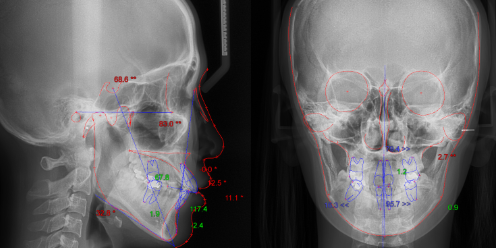

교정치료는 눈으로만 확인하고 정밀한 치료계획을 세울 수 없습니다.

구강 전반 및 얼굴뼈 부위까지 광범위한 진단을 통해 육안으로는 파악하기 어려운 부분까지 살펴볼 수 있습니다.

약2년간 이어지는 치료과정동안 의료진의 판단에 도움을 주어 올바른 치료가 될 수 있도록 도와주는 장비입니다.

안모를 분석합니다.

교정치료 결과 후의 모습을 확인 할 수 있습니다.

구강 및 안모의 정보를 모르페우스3D 장비를 이용해 입체적으로 파악 가능합니다. 환자의 입장에서 결과값에 대하여 의료진과 소통을 할 수 있다는 점에서 큰 도움이 됩니다.